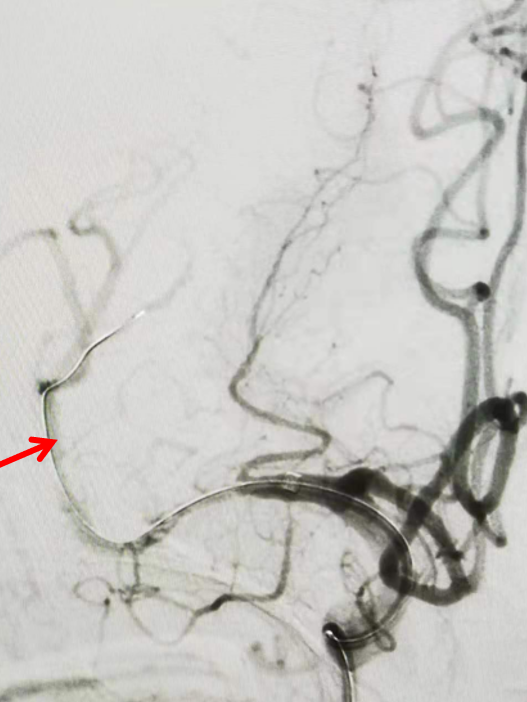

Headway17微导管在3m的Synchro-14导丝辅助下,谨慎通过闭塞处(左图箭头示),撤出微导丝,微导管造影证实在在闭塞远端血管真腔(右图箭头示)。

通过微导管给予路径图,而后将微导丝置于闭塞血管远端后撤出微导管(图箭头示)。